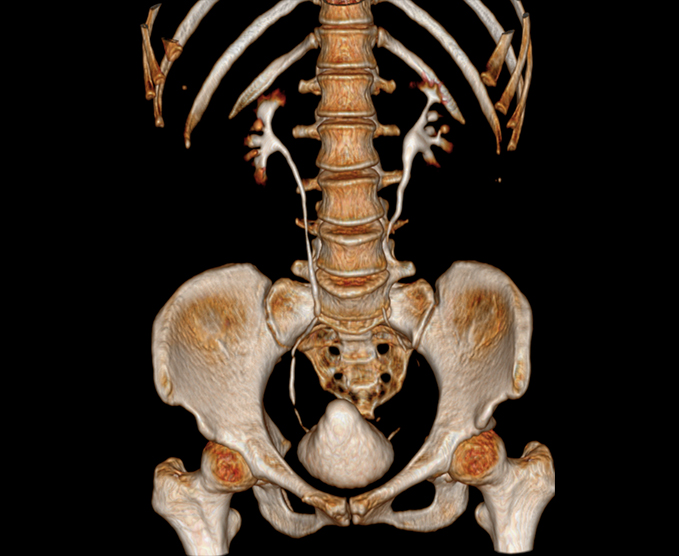

- Columna vertebral

- Abdomen superior e inferior